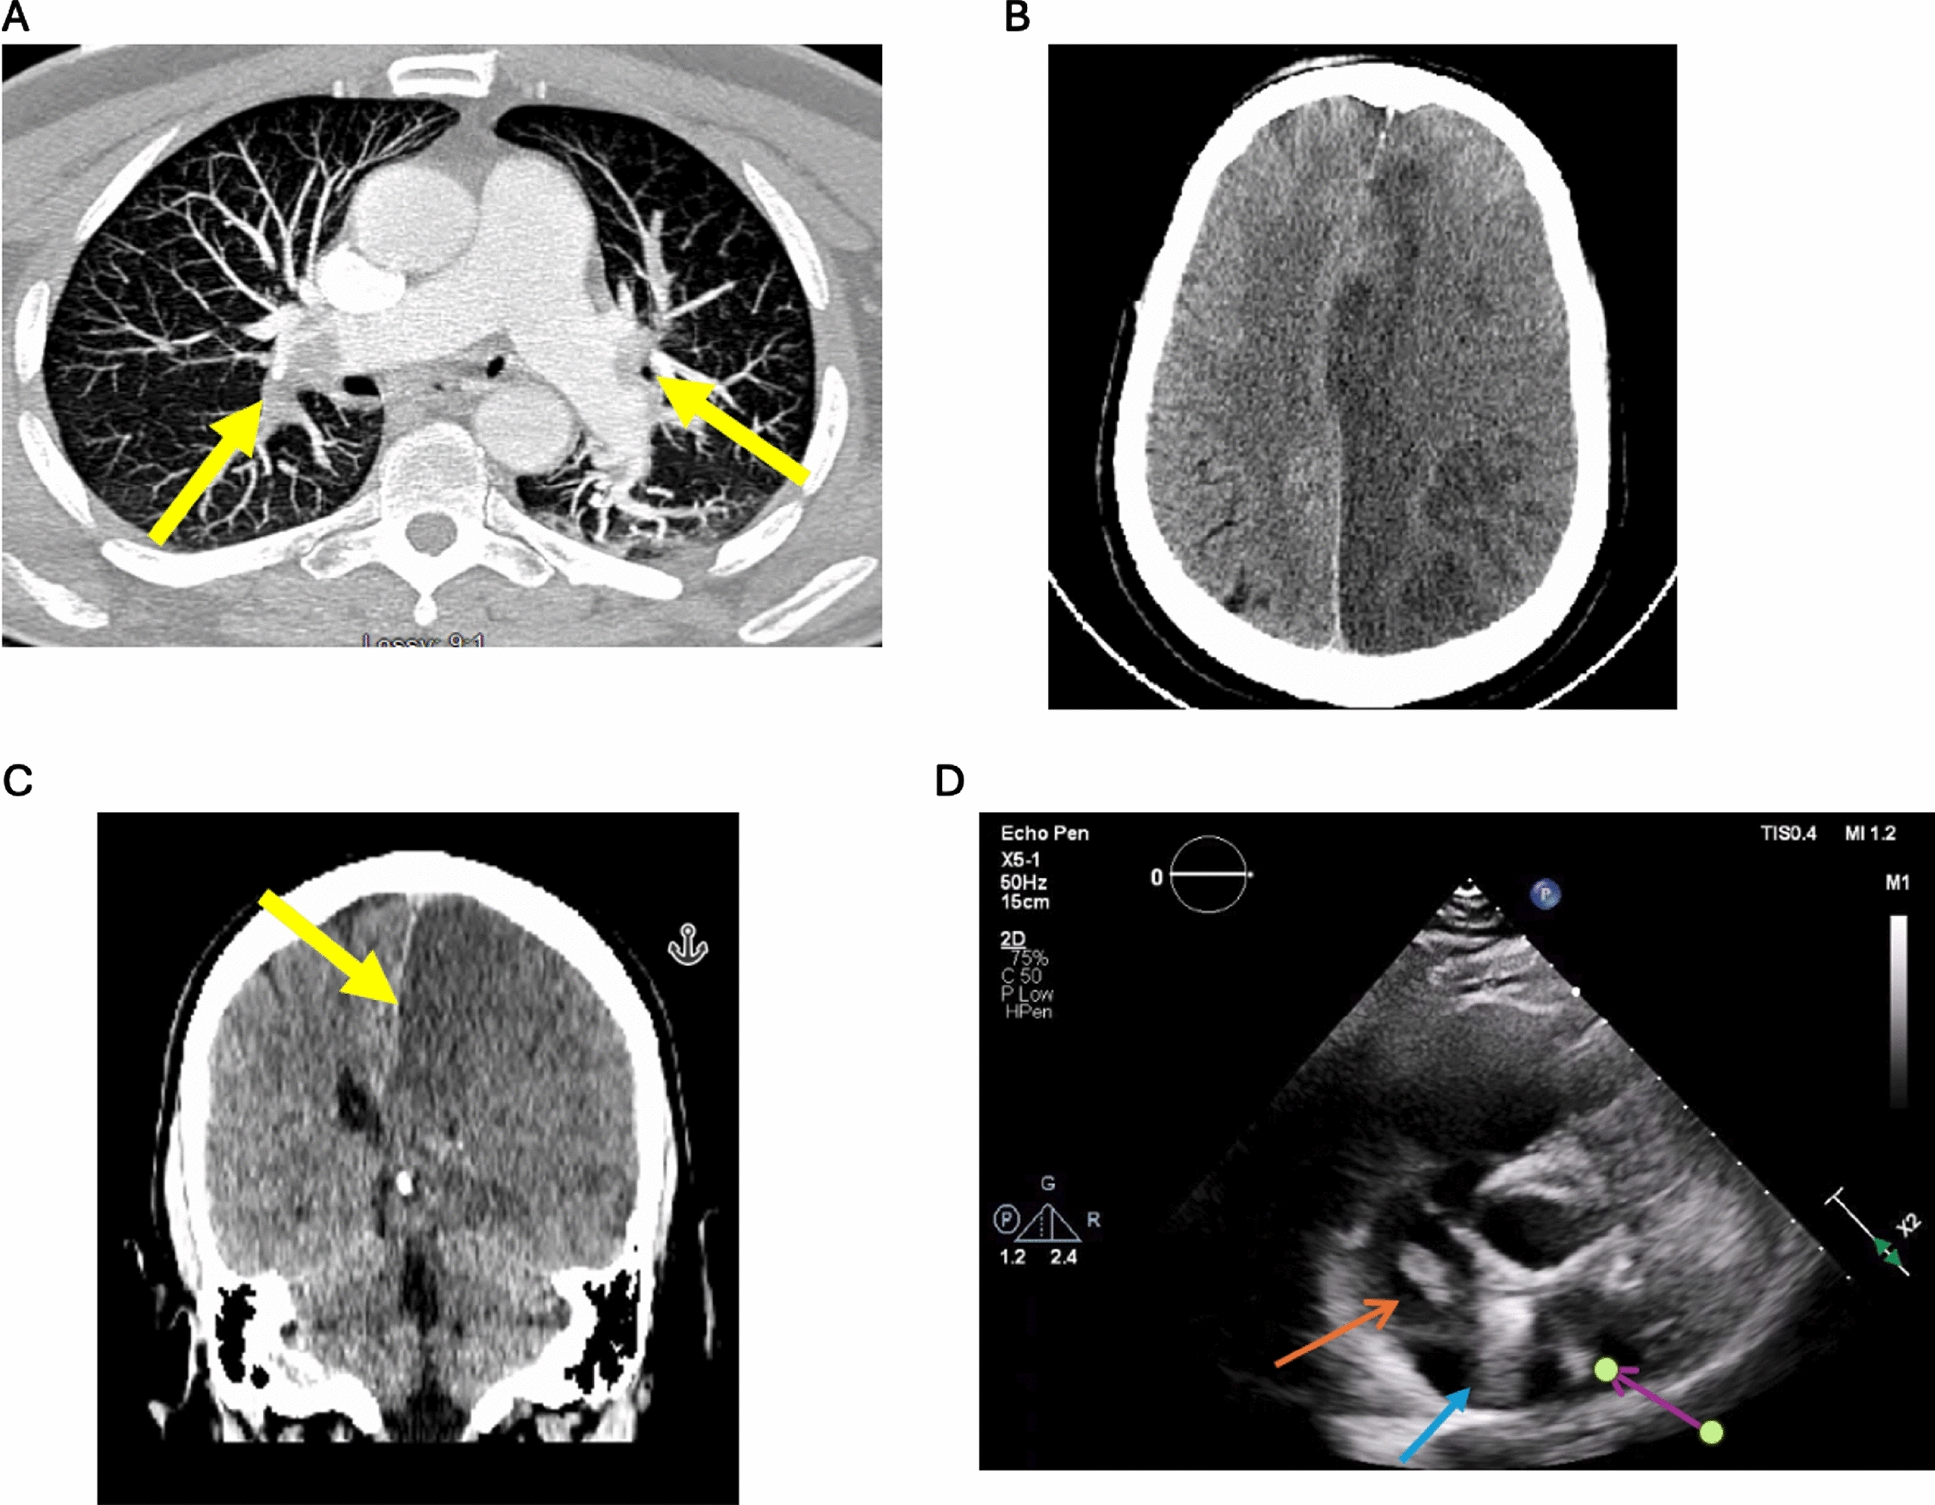

A 58-year-old man with a recent history of coronavirus disease 2019 infection was found down with no significant sign of external trauma. He initially had a negative head computed tomography (CT). However, CT angiography chest examination revealed bilateral pulmonary emboli (Fig. 1a). He was admitted to the intensive care unit for hemodynamic monitoring and therapeutic anticoagulation therapy was started. He subsequently developed hemiplegia, which was first discovered during a spontaneous awakening trial. Repeat noncontrast head CT, performed immediately upon discovery of hemiplegia, revealed extensive stroke findings seen in Fig. 1b and c, which demonstrate infarction involving the entire left cerebral hemisphere including the anterior, middle, and posterior cerebral arteries with edema, midline shift, and subflacine herniation, necessitating urgent decompressive hemicraniectomy.

Fig. 1

a Contrast-enhanced computed tomography (CT) angiography of the chest, axial view. Bilateral pulmonary emboli are visualized in the main pulmonary arteries, demonstrating significant thromboembolic burden (arrows). b Noncontrast CT of the head, axial cut. A large left intracranial infarct of the entire left cerebral hemisphere including the anterior, middle, and posterior cerebral arteries with edema and midline shift. c Noncontrast CT of the head, coronal cut. Large left intracranial infarct with subfalcine herniation (arrow). d Transthoracic echocardiography, parasternal short-axis view. A thrombus in transit is identified extending from the right atrium (orange arrow) through a patent foramen ovale (blue arrow), moving into the left atrium (purple arrow).